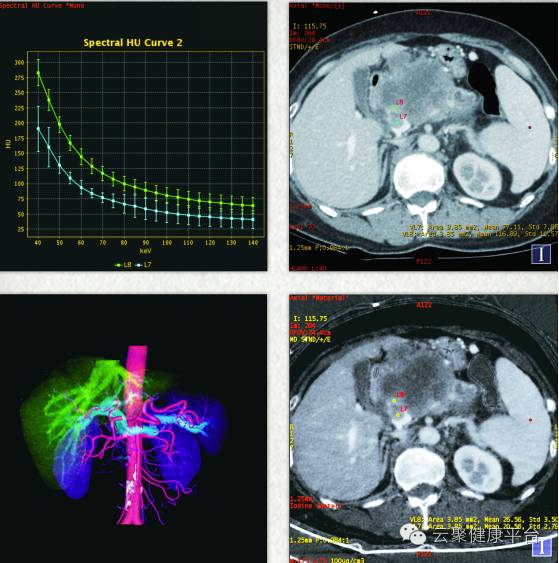

CT之剑中刀“屠龙刀”:宝石能谱CT是CT之剑中刀“屠龙刀”,能谱分析可对肿瘤病变的性质进行鉴别诊断,对于小病灶的敏感性可与PET/CT相媲美。能谱CT凭借其单光子成像与物质分离技术,突破了传统形态学的观察,通过能谱变化来辨别内部物质成分,对于鉴别肿瘤良恶性以及肿瘤的同源性有重要意义。

宝石能谱CT鉴别肿瘤良恶性以及肿瘤的同源性